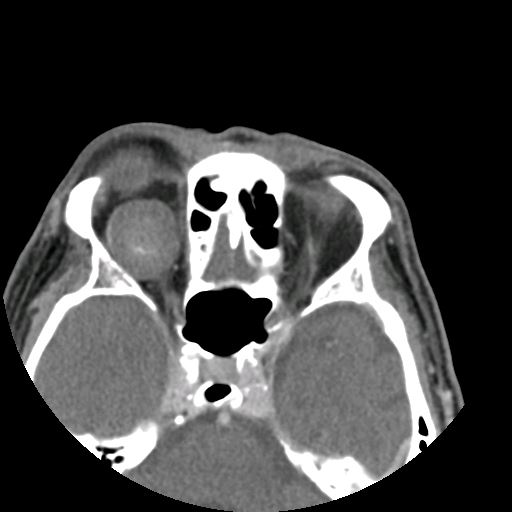

ORBITAL SURGERY

• Tumors